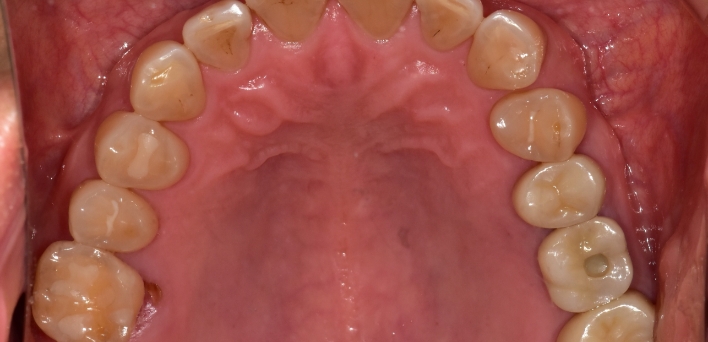

After After

2020.02.30

※ 더서울치과의원은 의료법을 준수하며 위 케이스는 실제 환자의 동의를 얻은 사례로 치료 전, 후가 동일한 환경에서 촬영되었습니다.

환자 케이스에 따라 부작용이 발생할 수 있습니다. 이 부분은 의료진의 충분한 상담과 체크를 통해 예방하고 줄일 수 있습니다.

[임플란트 부작용] 수술 후 관리가 소홀할 경우 출혈, 주위염 등의 부작용이 발생할 수 있어 구강 위생을 철저히 유지하고, 정기적인 검진을 통해 상태를 점검하는 것이 중요합니다.

위, 아래 6개씩 식립

디지털 풀아치 임플란트